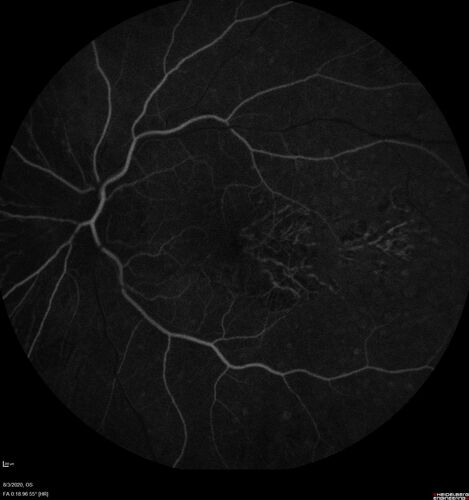

Age-related macular degeneration - Geographic Atrophy - Intermittent CME left eye from CRVO, Anemia, Diabetes

79 year old female - 3 years post CRVO in the left eye (20/32 VA) with intermittent CME.  Left eye is the better eye.  Vision is stable since 2 years ago

PMHx: Type II DM x 20 years, Chronic Anemia, Hyperlipidemia

VA 20/200 OD, 20/50 OS (usually 20/40)